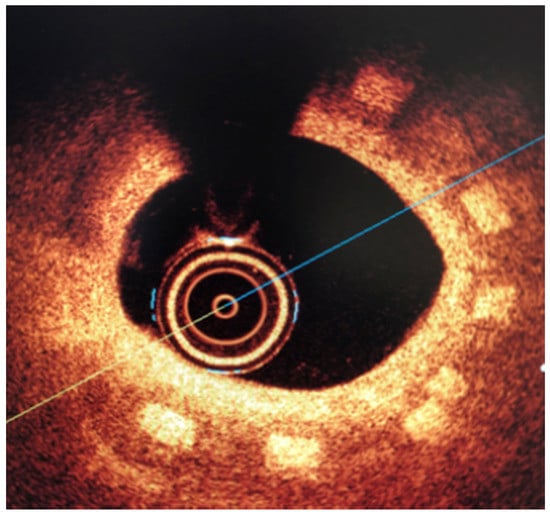

3.2. Biological Response

All three stents were implanted successfully. In coronary angiography stents showed enough radial force to support overstretched vessel (Figure 13). The OCT has shown good stent apposition and the analysis has shown lumen enlargement post implantation 24% as shown in Figure 13c. At 28-day follow-up, all stents were covered with neointima, and struts embedded. Interestingly the signs of material hydrolysis were observed thus proving the polymer amorphic properties (Figure 14).

Figure 13.

Acute outcome after PLGA/PLLA blend polymer stent implantation in coronary angiography (a) and optical coherence tomography (b). Lumen area increase before and after implantation (c). Geometrical view of vessel after stent implantation (d).

Figure 14.

Optical coherence tomography at 28 days follow-up show optimal vascular response and stent geometry. Stent struts show blurred image, a sign of early hydrolysis (rectangle).

The results presented in the mathematical modeling has shown sufficient radial force, inflate, expand and implant a tested stents in the coronary vessel. This was validated by mechanical radial force tests as well as implantation in the in-vivo, porcine in-stent restenosis model. The implanted stents provided sufficient strength to withheld the compression of on oversized vessel. The struts were well apposed. At long-term follow-up the stent areas remained similar, thus confirming time-dependent tensile and radial strength. This pivotal study showed optimal neointimal coverage of all stents struts which were embedded without excess of neointima. Additionally, the struts in OCT were absorbable to light from OCT, in contrary to immediate effect after implantation. This could be the result of hydrolysis, and amorphous character of the tested polymer. This requires however further investigation of the explanted material.